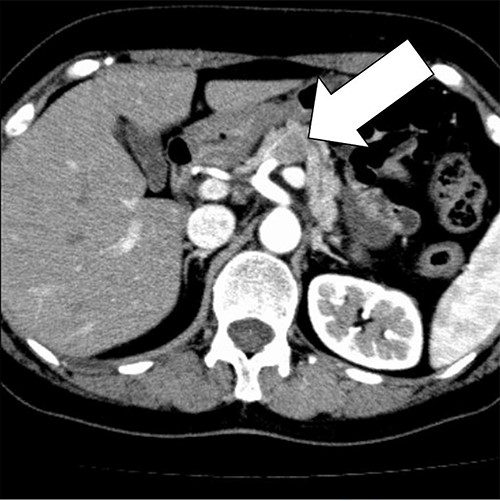

A 58-year-old woman began to have back pain and upper abdominal pain and then visited a hospital. Laboratory findings showed mildly elevated total bilirubin 1.3 mg/dl and high amylase 466 IU/l; however, peripheral blood, liver and kidney functions were within normal limits. Tumor markers were within normal limits: CEA 1.1 ng/ml, CA19–9 24.3 U/ml. An abdominal computed tomography (CT) scan revealed a 2-cm mass with mild contrast effect in the pancreatic body. There was a little tendency to invade the surrounding area, which was different from typical pancreatic ductal carcinoma (Fig. 1). Abdominal ultrasonography (US) showed a 19.4 × 12.6 mm mass in the pancreatic body. It was a hypoechoic mass with a clear boundary, smooth and homogeneous interior. Pancreatic duct dilation was observed more clearly than around the mass (Fig. 2).

An abdominal CT scan revealed a 2 cm mass with mild contrast effect in the pancreatic body. There was a little tendency to invade the surrounding area, which was different from typical pancreatic ductal carcinoma.